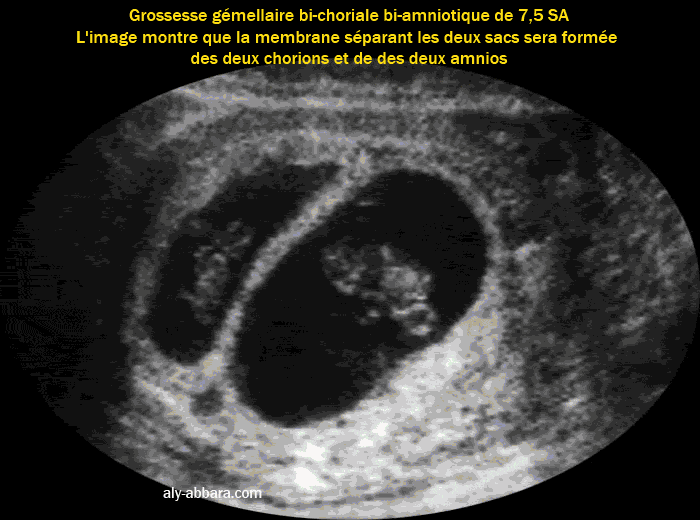

• Image échographique montrant le type de placentation d'une grossesse gémellaire bi-amniotique bi-choriale obtenue par fécondation in vitro (faux jumeaux).

• On peut remarquer que cette cloison (ou membrane inter-ovulaire) qui sépare les deux cavités ovulaires sera composée des deux amnios en dehors et des deux chorions au centre, car la cavité amniotique va grandir progressivement pour occuper l'espace habité par le cœlome externe, puis l'amnios qui limite cette cavité amniotique va coller au chorion au niveau de la cloison inter-ovulaire, de la plaque choriale du placenta et au niveau des parois utérines.

• Le raccordement de la membrane inter-ovulaire au niveau de la paroi utérine prend l'aspect de " λ " ; ce raccordement est connu sous le nom du signe Lambda (au premier trimestre de la grossesse) et le signe de Twin Peak (au 2e et 3e trimestres de la grossesse).

• Cette forme de placentation (bi-choriale ; bi-amniotique) se voit dans toutes les grossesses gémellaires dizygotes (faux jumeaux) et dans 30 % des grossesses gémellaires monozygotes (vrais jumeaux).